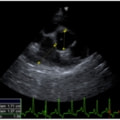

D:La/Ao比の重度拡大あり

左側胸壁心尖部領域を最強点とするLevine 5/6の収縮期性心雑音が聴取された。安静時にも咳が認められる。胸部レントゲン検査において重度の心拡大が及び肺水腫が認められた。超音波検査では、重度の僧帽弁閉鎖不全、三尖弁閉鎖不全が認められた。三尖弁逆流速度から肺高血圧症が示唆された。ACE阻害薬、ピモベンダン、硝酸イソソルビド徐放剤、ベラプロストナトリウム、利尿剤としてフロセミド及びスピロノラクトンを用いて治療を行っている。